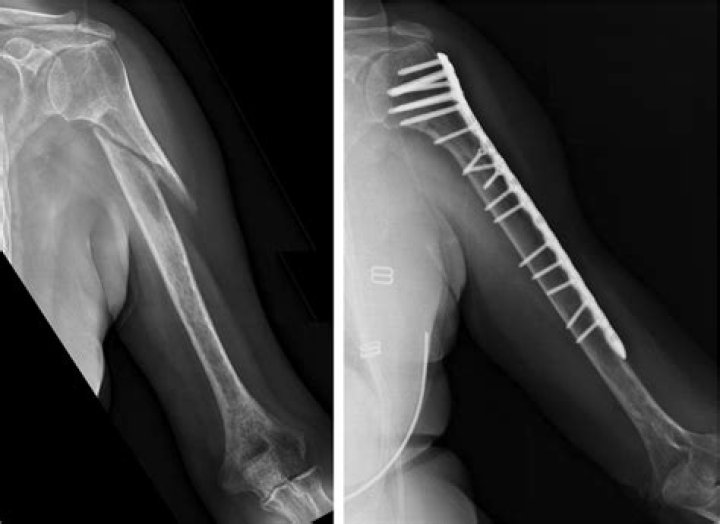

Surgeons may recommend an operation to fix the broken humerus if it is broken into many pieces, if the bones are far apart, if the bone sticks out through the skin, or if the nerves or blood vessels are injured.

Most fractures of the proximal humerus can be treated without surgery if the bone fragments are not shifted out of position (displaced). If the fragments are shifted out of position, surgery is often performed to allow earlier mobility.

In this surgery, the bones are repositioned to back to where they should be and then held in position with screws, plates, heavy sutures or other means. The bones will go on to heal, usually within 6-10 weeks.